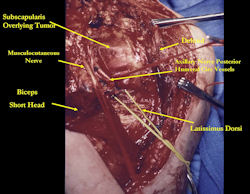

Examples of radical limb sparing surgeries for osteosarcomas in various anatomic locations (distal femur, proximal tibia, proximal humerus, scapula)

In each case, the tumor and bone from which it arose were resected. This required meticulous dissection, mobilization and preservation of adjacent pertinent neurovascular structures. In each case presented here, the defect was reconstructed with a special modular segmental tumor prosthesis. This also replaces the adjacent joint in many instances.

Proximal Humerus: Radical Limb Sparing Extra-Articular Resection and Prosethetic Reconstruction